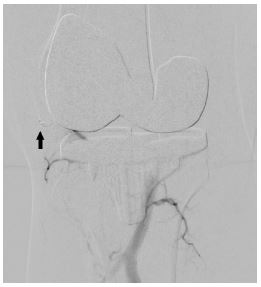

In view of continued knee joint swelling, the patient underwent right lower limb angiography the following week through the right femoral artery approach which identified a Pseudoaneurysm arising from the inferior medial genicular artery. This was embolized using 250 microns’ particles- embospheres and 2mm push able coils. Selective angiogram performed from superior medial and lateral genicular artery showed abnormal blush and pruning was done using 250-micron embospheres (Figures 3,4 & 5). An Ice pack was placed over the knee while instilling embolic agent particles to cause vasoconstriction of the skin arterial supply to avoid ischemia.

Figure 5: Post embolization using particles- embospheres and coils (solid arrow) angiography shows non opacification of the pseudoaneurysm.